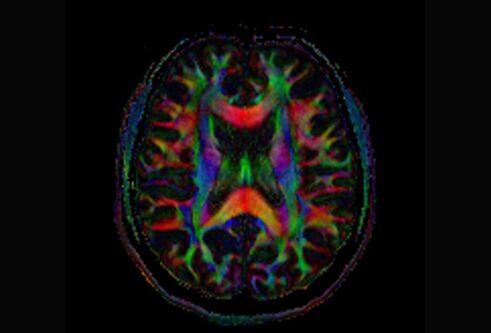

AI software tool aims to spot early signs of dementia from brain scans during routine appointments

Data scientists and clinical researchers will use brain scans from the entire Scottish population to build a software tool that they hope will be able to predict a person’s risk of dementia